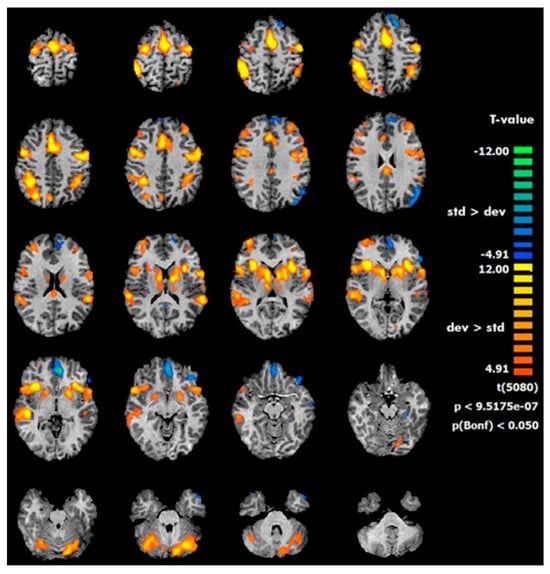

- Rusiniak, M.; Lewandowska, M.; Wolak, T.; Pluta, A.; Milner, R.; Ganc, M.; Włodarczyk, A.; Senderski, A.; Śliwa, L.; Skarżyński, H. A Modified Oddball Paradigm for Investigation of Neural Correlates of Attention: A Simultaneous ERP-FMRI Study. Magn. Reson. Mater. Phys. Biol. Med. 2013, 26, 511–526. [Google Scholar] [CrossRef]